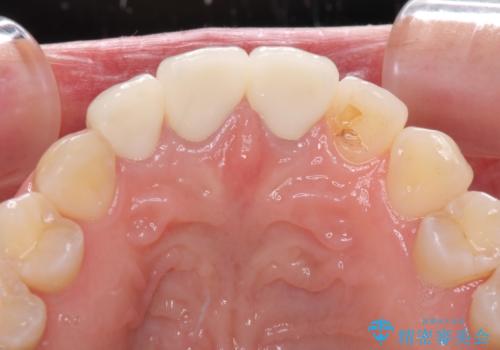

前歯の審美歯科治療 オールセラミッククラウンと部分矯正

前歯は一部根管治療を行った後にオールセラミッククラウンに補綴することとしました。

補綴治療に先立ち、下顎前歯の部分矯正を行い、前歯の咬み合わせの安定性向上を図りました。

当初は上顎の補綴治療のみを希望されていましたが、仮歯装着期間に上下の前歯の接触が気になったため、部分矯正を行うこととしました。